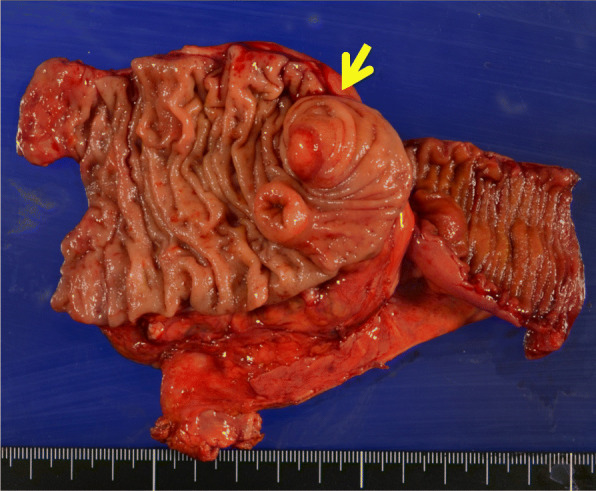

The excised specimen contained a submucosal tumor-like protruding lesion at a location consistent with the appendiceal orifice. The appendix was very short and showed marked deformity (Fig. 4).

Fig. 4.

The excised specimen contained a submucosal tumor-like protruding lesion (arrow) at a location consistent with the appendiceal orifice